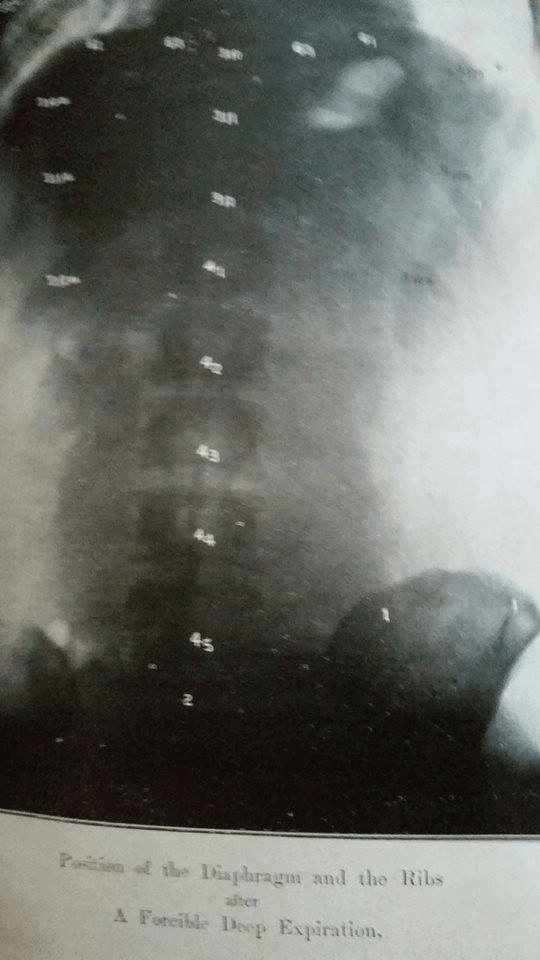

This x-ray shows position of Diaphragm and ribs after forcible deep expiration. Research was carried out by Dr.Popat Prabhuram Senior Vaidya Gogte and others in Prabhuram Ayurvedic College in 1935. The firmly believe that Yoga has capacity to prevent and even cure diseases like Cancer, paper was also publish everything destroy when old building of Prabhuram Ayurvedic Vidyalaya collapse in 1987 without any support by Govt or populace. After West intervene again in 1990’s again everywhere Yoga, Yoga and Ayurveda, Ayurveda. My respect to those Vaidya’s. Pranam.